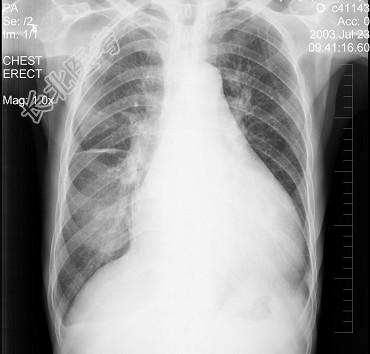

- 单项选择题患者女性,70岁, 胸闷、气逼数年,无明显发热、胸痛, 如图最可能的诊断是 ( )

A、心包积液并右水平裂积液

B、心包积液并右下肺炎

C、心包积液并右斜裂积液

D、心包积液并右双叶间裂积液

E、气胸